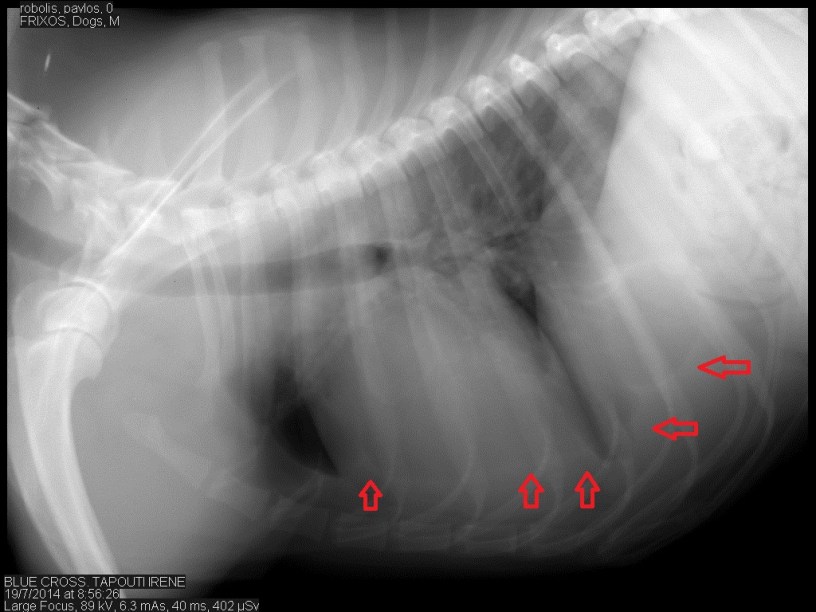

Ευρήματα: Στον υπέρηχο κοιλίας δεν υπήρχαν ευρήματα για αυτό τον λόγο συνεχίστηκε η εξέταση και στη θωρακική κοιλότητα ώστε να βρεθεί η αιτία των αυξημένων λευκών αιμοσφαιρίων ( στοιχείο που συνήθως δείχνει πως υπάρχει κάποια συλλογή, εφόσον έχουν αποκλειστεί άλλα αίτια). Η καρδιά ελέγχθηκε φυσιολογική σε ηχοδομή και λειτουργικότητα. Στη διάρκεια της εξέτασης της καρδιάς η περιοχή γύρω από αυτήν και μεταξύ των λοβών του πνεύμονα ήταν αρκετά υπερηχογενής. Στα πρόσθια πνευμονικά πεδία ανιχνεύθηκε μικρή συλλογή υγρού η οποία και παρακεντήθηκε. Στη συνέχεια έγινε ακτινογραφία θώρακος για να εκτιμηθεί η κατάσταση του πνευμονικού παρεγχύματος και της θωρακικής κοιλότητας. Στην ακτινογραφία βρέθηκε πως οι κορυφές των οπίσθιων λοβών του πνεύμονα δεν ήταν οξύληκτοι στοιχείο που μας δείχνει πως πιθανότατα έχει αναπτυχθεί ινώδης ιστός μεταξύ των λοβών και του υπεζωκότα. Εικόνα χρόνιας φλεγμονής. Έγινε λήψη του υγρού όπου δεν βρέθηκαν μικροοργανισμοί αλλά αφθονία ουδετερόφιλων και μακροφάγων κυττάρων. Λαμβάνοντας όλα τα ευρήματα υπ’ όψιν καταλήγουμε στο συμπέρασμα πως πρόκειται για μια χρόνια άσηπτη φλεγμονή του υπεζωκότα η οποία είναι παραγωγική. Σε περίπτωση που υπάρξει ξανά συλλογή μπορεί να γίνει πλευροδεσία με ενδοθωρακική χορήγηση ιωδιούχου τάλκ. Η τεχνική αυτή εφαρμόζεται σε χρόνιες πλευρίτιδες κυρίως από νεοπλασματικά αίτια.

τα βέλη δείχνουν την πορεία των λοβών του πνεύμονα.